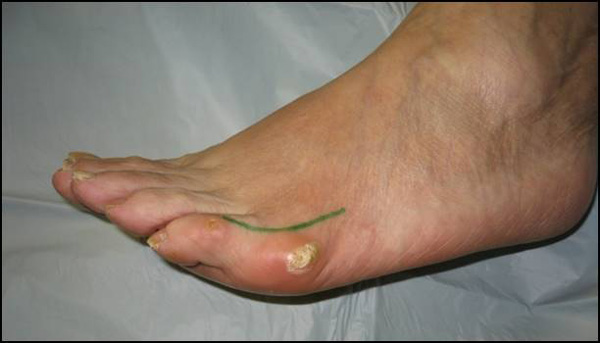

Schmerzen lateral, manchmal auch plantar, selten dorsal am Metatarsale V Köpfchen mit Schwielenbildung, akuter oder chronischer Bursitis.

Abb. 1a, b, c: Klinisches Bild eines Schneiderballens von dorsal, schräg und lateral.